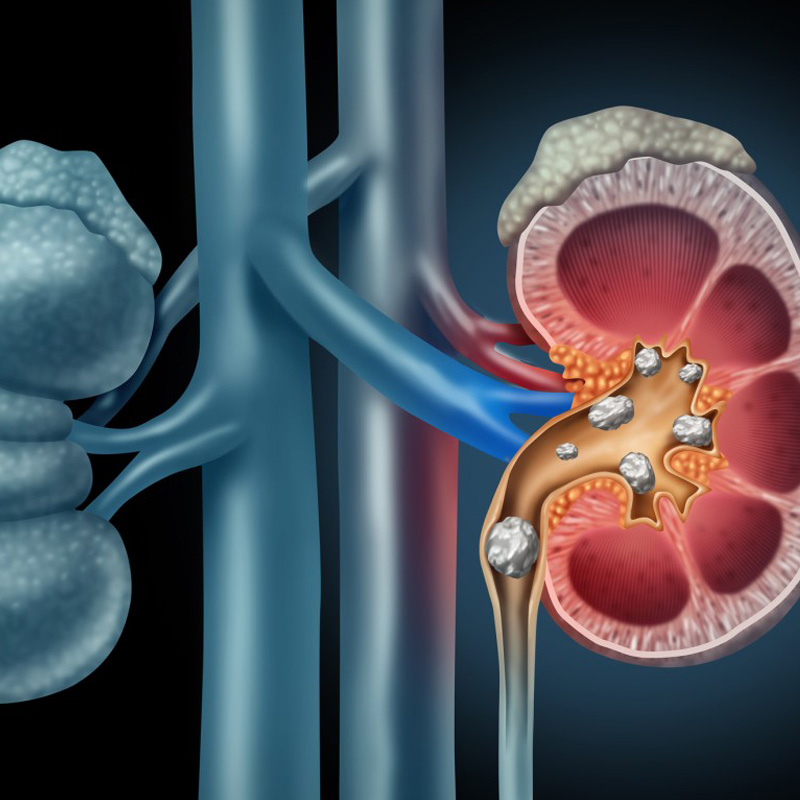

5. Urinary obstruction: Cancer, prostate enlargement, blockage due to stone

4. Urinary tract diseases such as stone, blockage, tumor